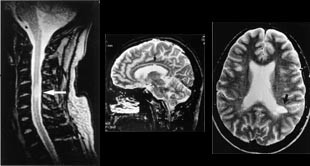

Svulster kan opptre i alle aldre og med høyst forskjellig intrakranial lokalisasjon. Ved bruk av flere ulike pulssekvenser og snittplan kan MR fremstille en svulst bedre enn andre tilgjengelige metoder. MR er således bedre enn CT til å identifisere og nøyaktig lokalisere svulsten. Samtidig forbedres fremstillingen av tumormorfologien, effekten på omkringliggende hjernevev og store intrakraniale blodkar. MR identifiserer solide og cystiske tumorkomponenter så vel som kontrastmiddeloppladende eller ikke-oppladende svulstvev (fig 1, 2 ). Ofte finner vi ved MR hjernemetastaser som ikke er synlige selv med en god CT-undersøkelse. Disse egenskapene ved MR har derfor kunnet gi vesentlig informasjon med henblikk på valg av terapi.

MR gir verdifull informasjon hos pasienter med degenerative lidelser i columna. En av de store fordelene ved MR er at bein og bløtdeler kan demonstreres i samme bilde, men atskilles pga. forskjellige signaler. Foreløpig kan det være et problem at oppløsningen i bildene ikke er så god som i konvensjonelle røntgenbilder. Enkelte detaljer kan derfor fremstilles bedre ved konvensjonelle radiologiske metoder, f.eks. rotskjeder ved myelografi. Prolaps kan som oftest fremstilles tilfredsstillende med CT (19), men i de fleste tilfeller er MR-bildene lettere å tolke (fig 6) (5).